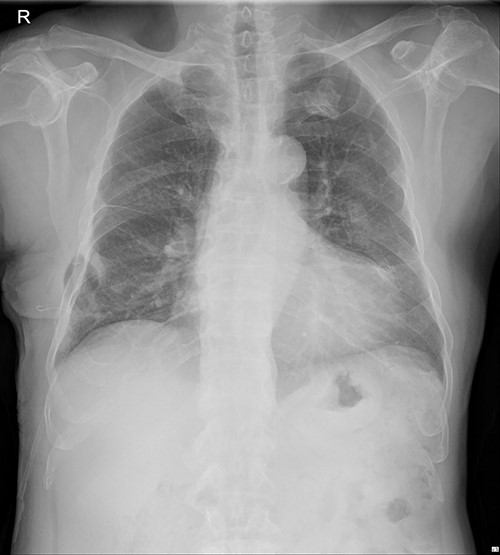

On 25 November 2021, a 68-year-old male, a victim of a motor vehicle accident, presented with multiple rib fractures and hemopneumothorax in the right hemithorax. On hospital Day 2, oxygen saturation gradually dropped under 90% despite proper support, and the patient’s right chest wall showed a newly occurred flail motion. We decided to stabilize rib fractures emergently. The operation was performed routinely, with bicortical screw fixation after exploration of the thoracic cavity. There were no specific intraoperative or postoperative events, and the patient was safely discharged from the hospital with stitches removed on hospital Day 17 (Fig. 1.).

Immediate postoperative chest X-ray after plates removal (24 February 2022).